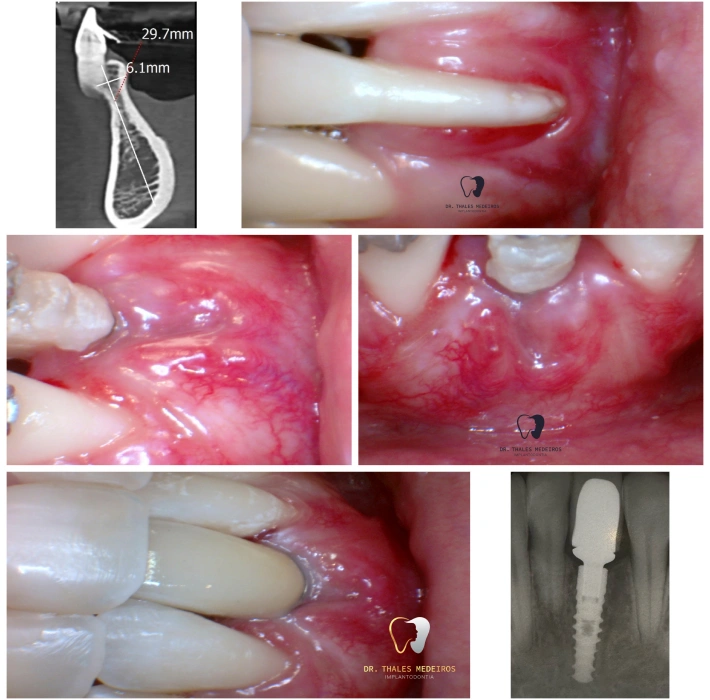

Cirurgia Plástica Periodontal e Periimplantar

Recupere a estética e a saúde do seu sorriso com a cirurgia plástica periodontal e periimplantar. O procedimento corrige retrações gengivais, remodela os contornos e prepara o sorriso para implantes e facetas. Entre os principais benefícios estão gengivas mais saudáveis, sorriso simétrico, harmonia estética e aumento da autoestima, garantindo resultados naturais.